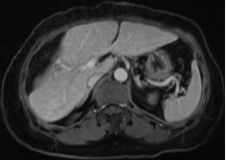

結(jié)腸腫瘤是指發(fā)生在結(jié)腸部位的腫瘤,可分為良性和惡性,結(jié)腸腫瘤早期癥狀不明顯,隨著病情發(fā)展,可能出現(xiàn)腹痛、便血、腸梗阻等癥狀,治療方法包括手術(shù)、化療、放療等,具體治療方案需根據(jù)患者的具體情況制定。

結(jié)腸腫瘤的生存期是一個復(fù)雜的問題,不能簡單地給出答案,早期結(jié)腸癌患者經(jīng)過積極治療,5年生存率較高,具體的生存期取決于上述多種因素,每個患者的情況都是獨特的。